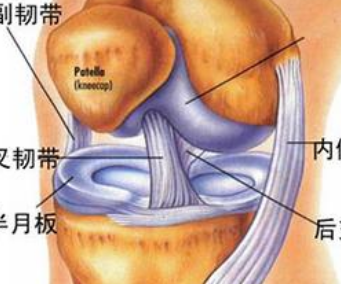

膝关节磁共振成像 诊断半月板损伤

600x339 - 86KB - JPEG